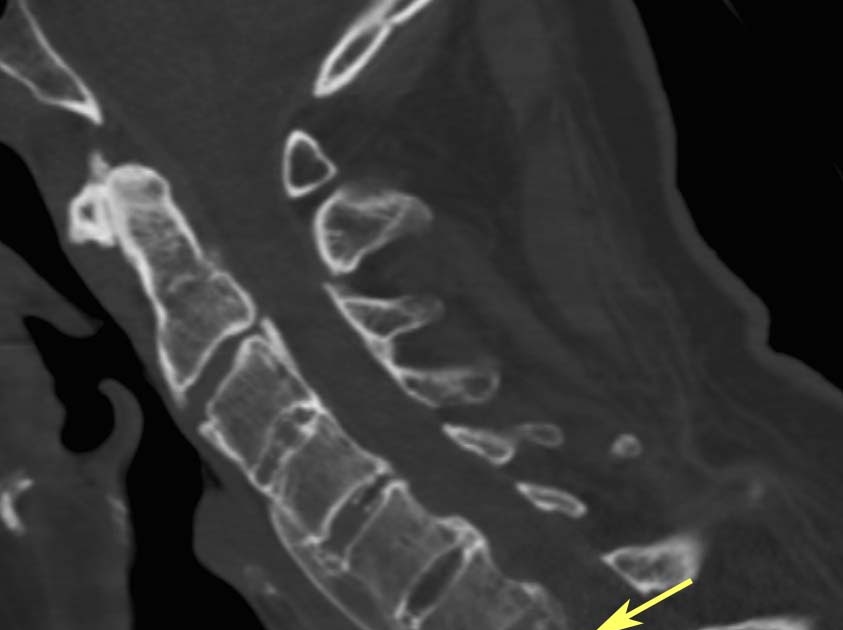

From radiologyinthai.blogspot.ca

RiT radiology Spinal Fracture in Ankylosing Spondylitis Can A Spinal Fracture Be Fixed Treatment and recovery for a spinal fracture depend on the severity and location. different surgical approaches as treatment for a fractured spine are available to repair fractured vertebrae, relieve pressure on. A minor fracture may heal. Without proper care, a spinal fracture that. pain from a spinal compression fracture allowed to heal naturally can last as long as. Can A Spinal Fracture Be Fixed.